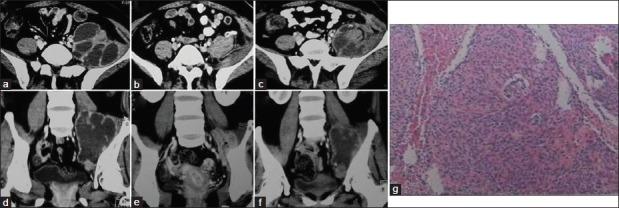

Iliopsoas abscess due to brenner tumor malignancy: a case report.

Chin Med J (Engl). 2015 Feb 5;128(3):423-4. doi: 10.4103/0366-6999.150126.